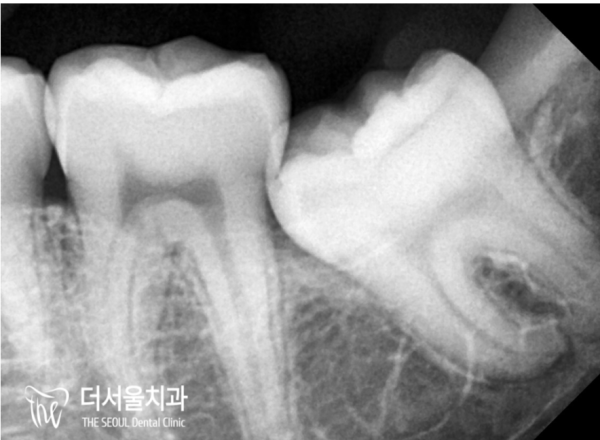

826fd3851ccac24696fbdfce7325926d_1697774654_7602.jpg

어려운 사랑니발치는, 통상적으로

매복사랑니, 옆으로 비스듬하게 누워있는 사랑니와 같이

비정상적인 형태로 자라난 사랑니를 의미한답니다.

Hard wisdom tooth extraction is usually

Ambush teeth, like wisdom teeth lying on the side

It is a wisdom tooth that has grown into an abnormal shape.